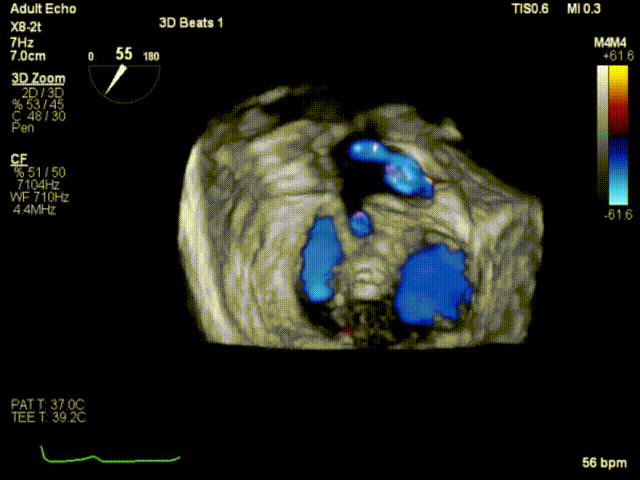

手术运用DSA与三维经食道超声心动图监测,通过患者股静脉穿刺房间隔途径建立夹合器输送轨道,将夹合器送进左心房,借助夹合器输送系统通过病变的二尖瓣部位,在心脏不停跳的状态下快速完成二尖瓣脱垂瓣叶的破获和夹合,夹合位置满意,超声提示反流降至1+,遂释放夹合器,反流最终程度为1+,结束手术,手术过程耗时一小时左右。

术后即刻超声心动图

术后即刻超声3D

纽脉医疗的Valveclip-M®系统是一款针对高危二尖瓣反流患者研发的经股静脉入路的缘对缘修复器械。该产品经股静脉入路,房间隔穿刺后到达左心房,通过操控输送器,实现夹合器的精确定位和夹合。应用Valveclip-M®系统的手术,术中无需体外循环,术后患者恢复较快,这为很多高危高龄患者及无法进行开胸手术的患者提供了新的安全、有效的治疗手段选择。本例应用Valveclip-M®系统的手术取得了良好的术后效果,患者二尖瓣反流量显著减少,症状明显减轻,目前已康复出院。